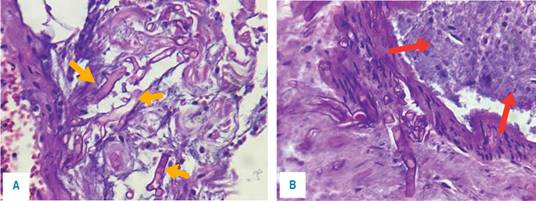

Figura 4: Pieza patológica con necrosis panmural asociada a trombosis arterial secundaria a microorganismos compatibles con Mucor sp.

Figura 5: Tinción con H-E en la que se identifica necrosis panmural asociada a trombosis arterial secundaria a microorganismos compatibles con Mucor sp.